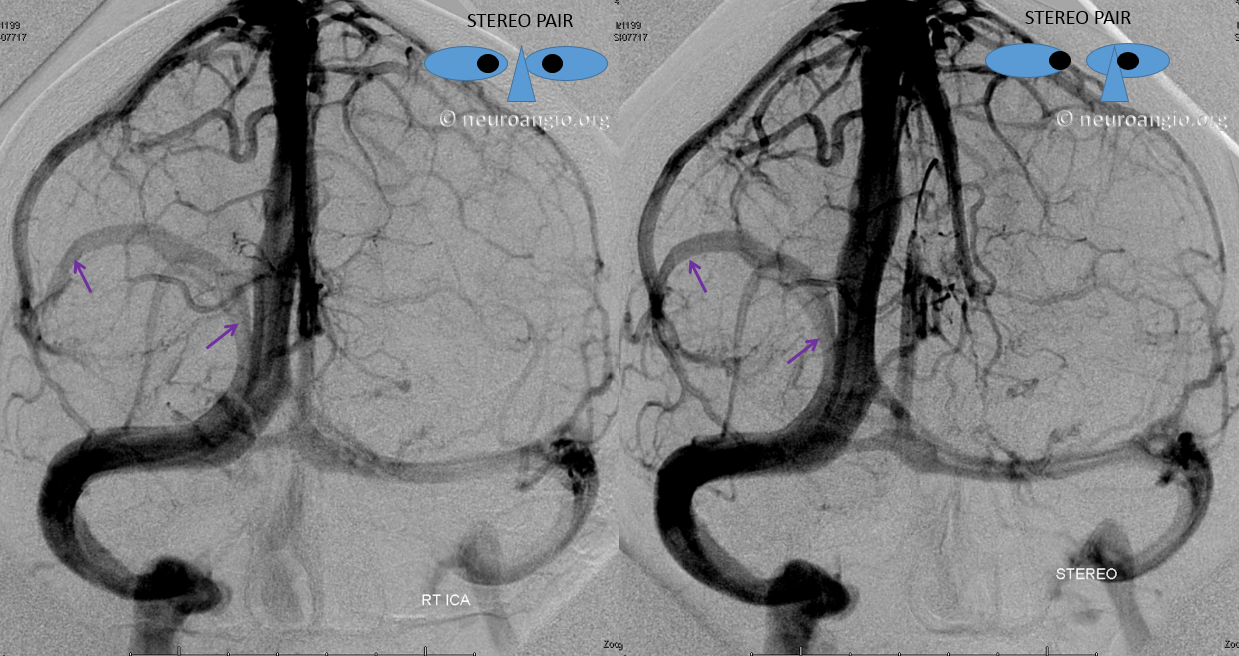

Here is an example of a right parieto-occipital sinus (purple arrows, stereo pair) which collects regional supratentorial and infratentorial veins, emptying into the transverse sinus. Again, this is really only of importance to a surgeon or interventionalist of a procedure in the area is being contemplated.